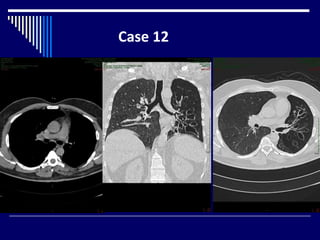

Case 12

Findings

• CT chest lung and mediastinal windows axial + coronal

views (1)

• Small, lucent left lung (2)

• ipsilateral mediastinal shift (1)

• Left sided bronchiectasis (1)

• Small left pulmonary artery (2)

Dx: Macleod's syndrome (3)